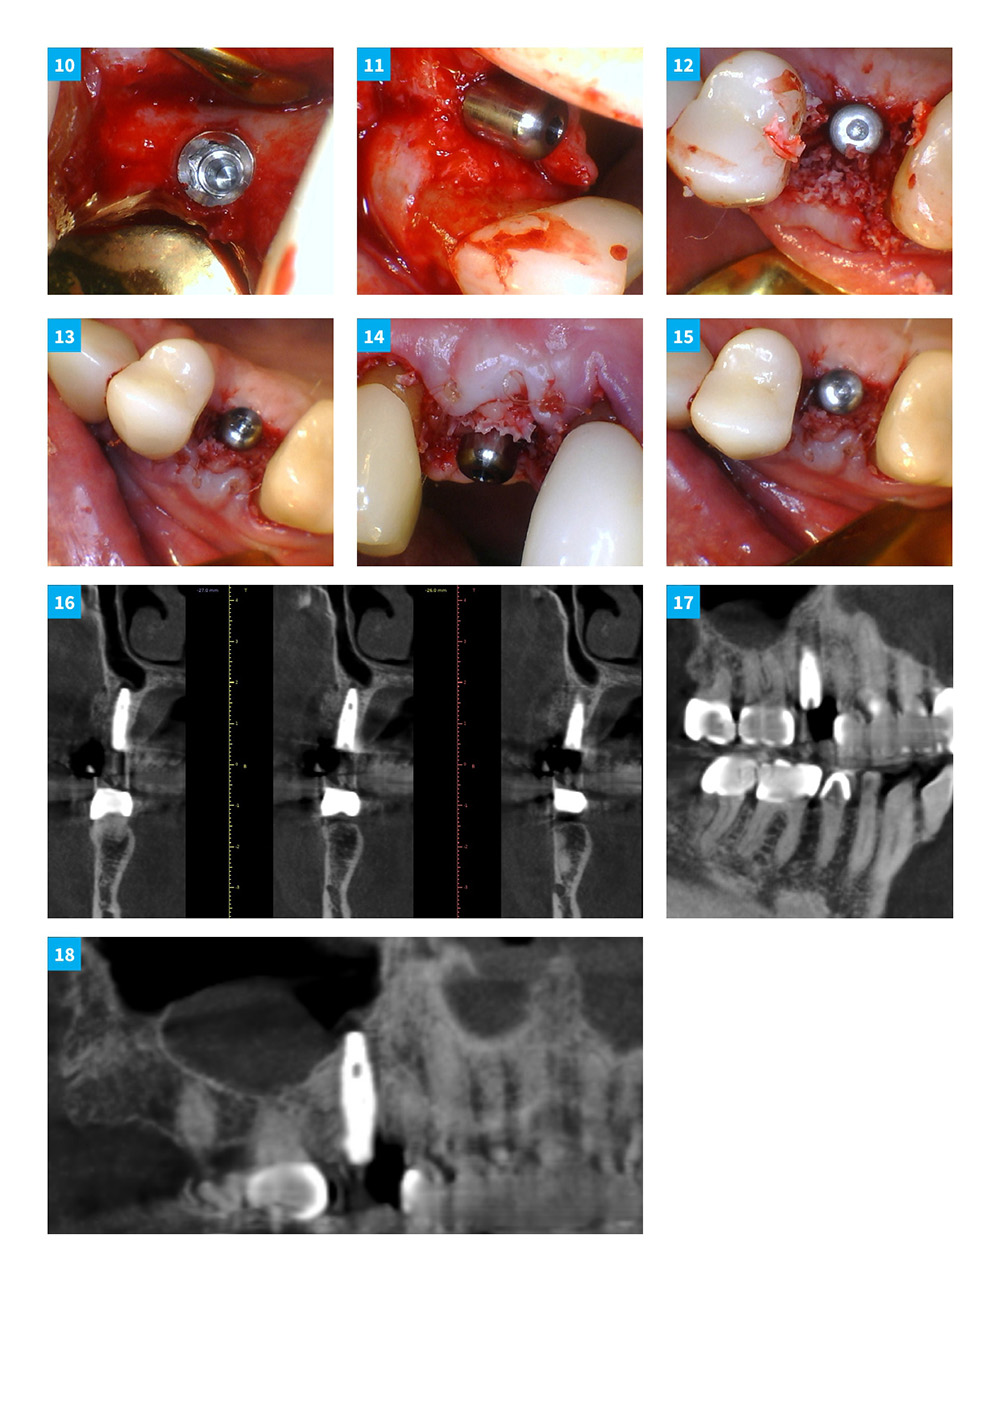

Dental Implant Continuum with DSI implants and products. Case 5